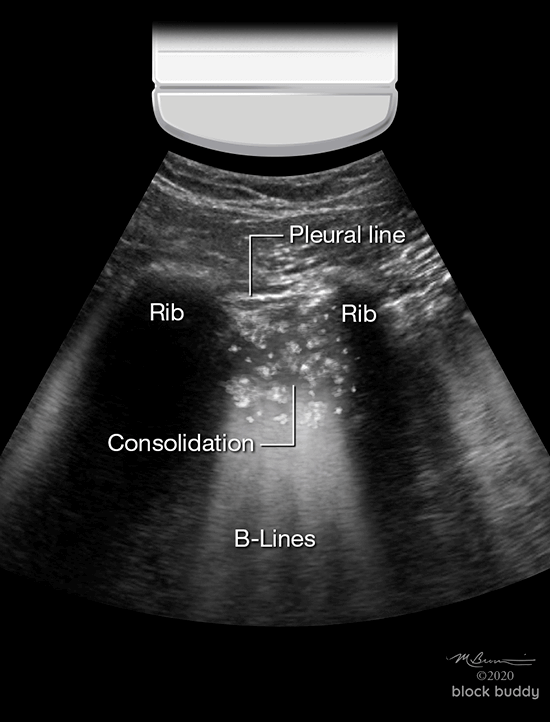

Consolidation

- Alveoli become filled with fluid: transudate, exudate, blood, or saline.

- Consolidation can be translobar or non-translobar.

- Translobar consolidation produces “tissue like sign” on ultrasound.

- Alveoli within entire lobe are filled with fluid.

- Causes hepatization: lung appears solid with a hypoechoic, homogenous echotexture similar to the liver.

- Lung dimensions are preserved.

- Non-translobar consolidation produces the “shred sign”.

- Most commonly seen consolidation.

- Involves a localized area or segment of the lobe.

- Within the lobe, there are areas of consolidation adjacent to normal aerated lung.

- The border between these areas area irregular and shredded.

- Commonly occur in the anterior chest.

- B-lines may extend from the shredded border to the bottom of the screen.

- Air bronchograms may be present in translobar or non-translobar consolidations.

- These hyperechoic specks or linear artifacts represent air within bronchi surrounded by fluid filled alveoli.

- These can be classified as static (motionless) or dynamic.

- Static air bronchograms indicate trapped air and do not move.

- Dynamic air bronchograms move with respiration and indicate the movement of air through fluid filled smaller airways.

- Consolidation most commonly occurs in patients with pneumonia.

- Patients with atelectasis may also present with a consolidation pattern on ultrasound.